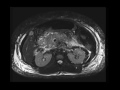

Acute pancreatitis

MRI and CT images demonstrate extensive peripancreatic edema and stranding, with associated enlargement and edema of the pancreatiuc parenchyma, in keeping with acute pancreatitis. Note that the entire pancreas enhances normally without evidence of necrosis.